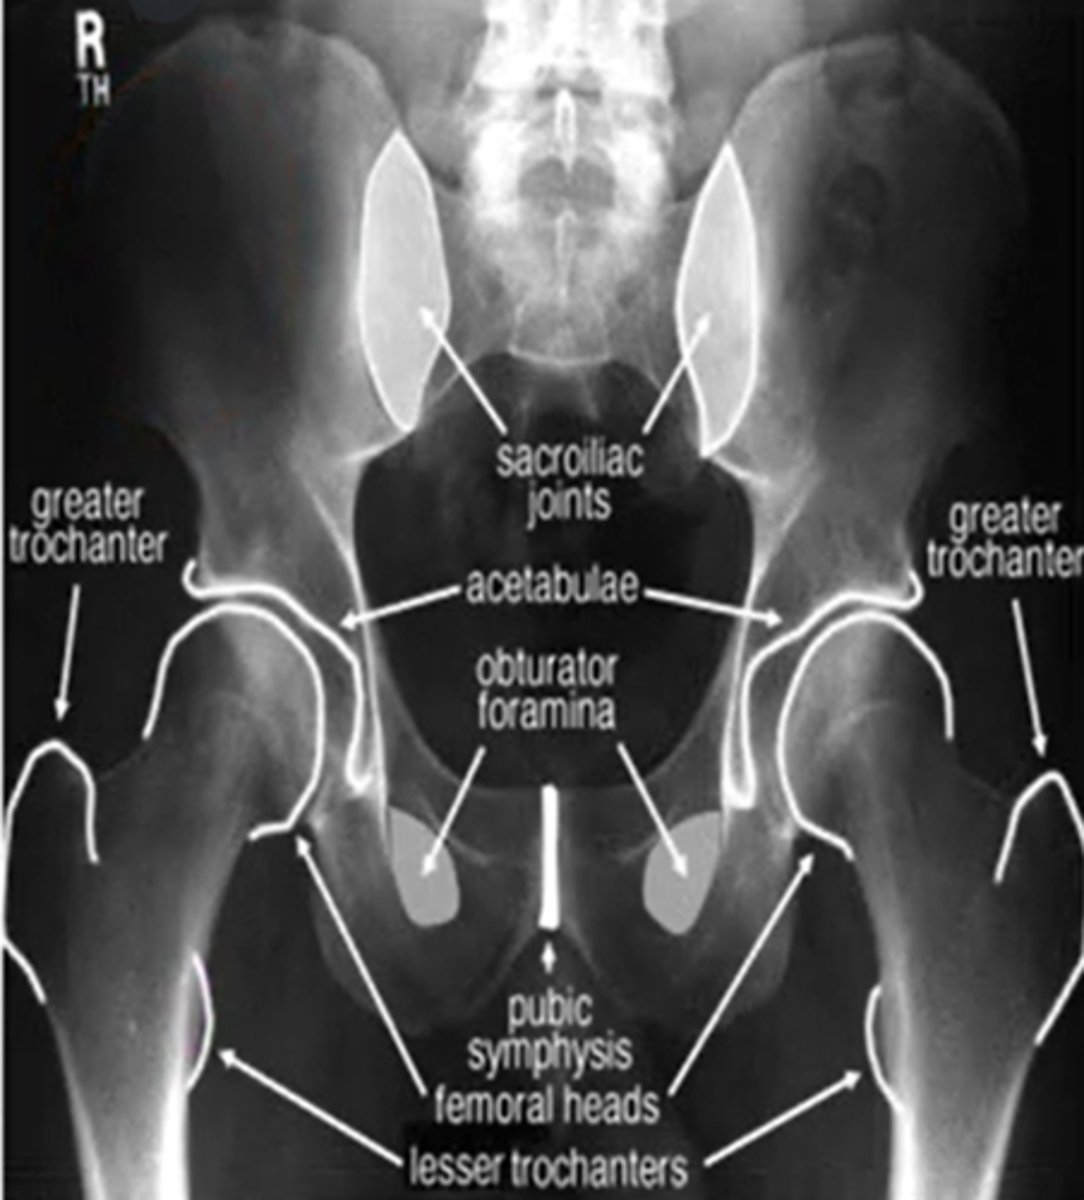

what are the three indications for hip radiograph

hip pain

avascular necrosis

stress fractures

for the pelvis what position is the hips for an AP view

IR 15-20 degrees

what are the three important portions of the acetabulum (ap view)

what position will the hip be if you want to see the medial portion of the femur (AP view)

frog leg